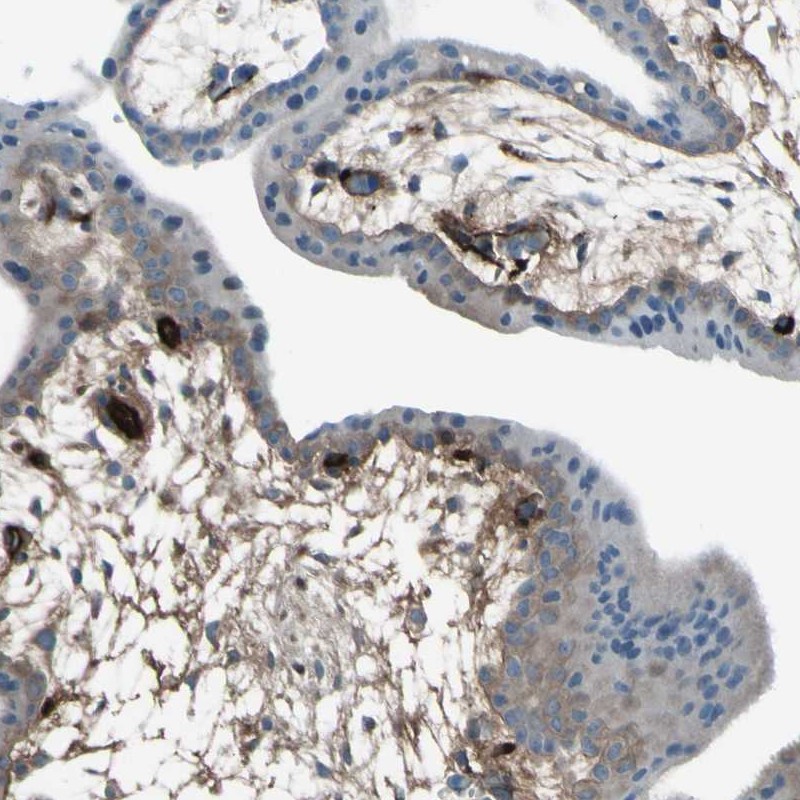

Immunohistochemical staining of human placenta shows extra cellular positivity.